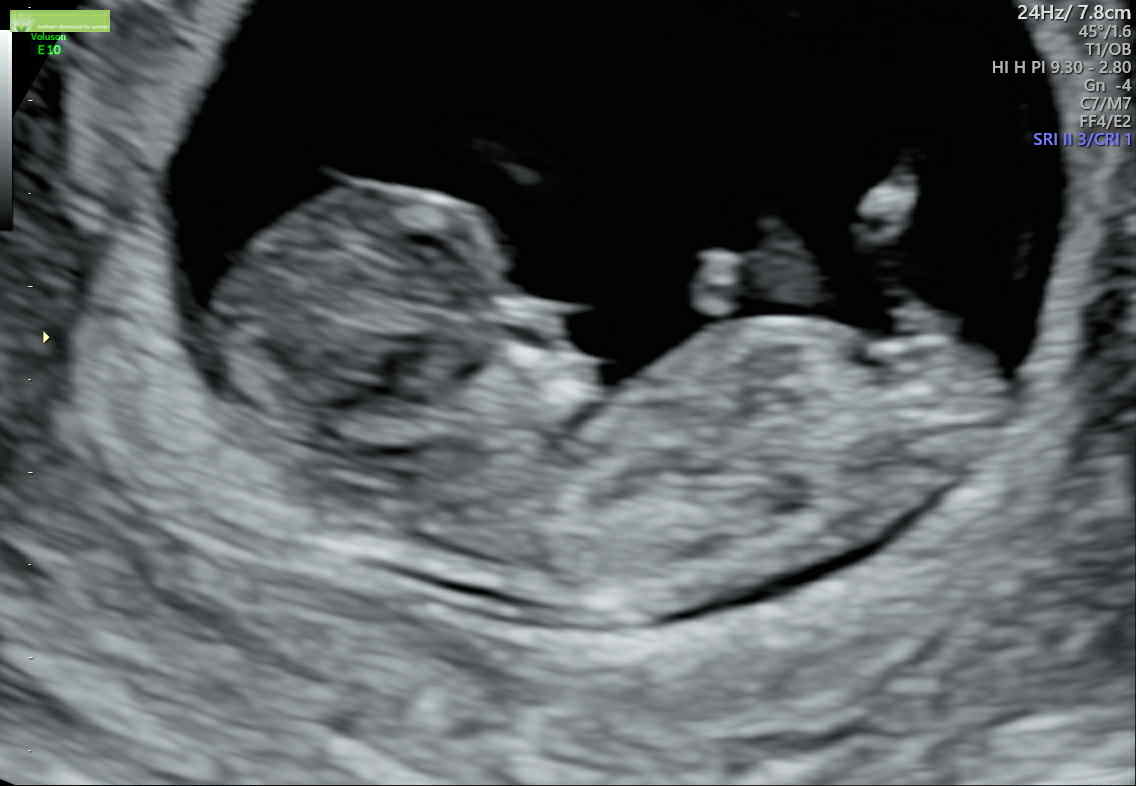

We're having a baby girl!